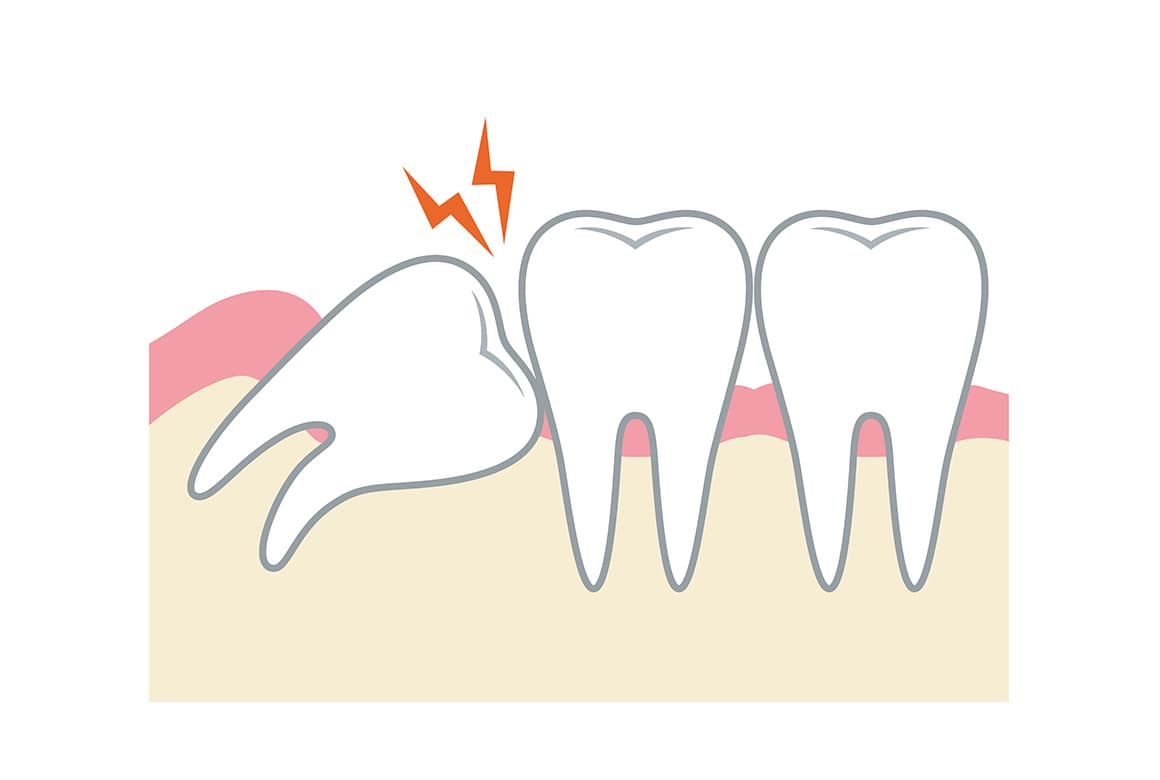

親知らずは、前歯から数えて8番目にあたる歯であり、大きな奥歯(大臼歯)の中では、前から数えて3番目に相当します。これは専門用語で、「第三大臼歯」と呼ばれる歯です。親知らずは生える場合と生えない場合がありますが、生える場合は、ほとんどのケースで10代後半から20代前半頃に生え始めます。

「親知らずの抜歯」といっても、5分で終わるものから、処置に1時間近くかかる症例までさまざまです。なお次のような場合は、放置するとトラブルが起きる可能性が高いため、抜歯をおすすめることがあります。

- きちんと生える見込みがない

- 大きな虫歯になっている

- 歯ぐきが腫れている

- 顎関節症(がくかんせつしょう)を起こしている

- 顎の骨の中に嚢胞(のうほう:膿や唾液の入った袋)ができている